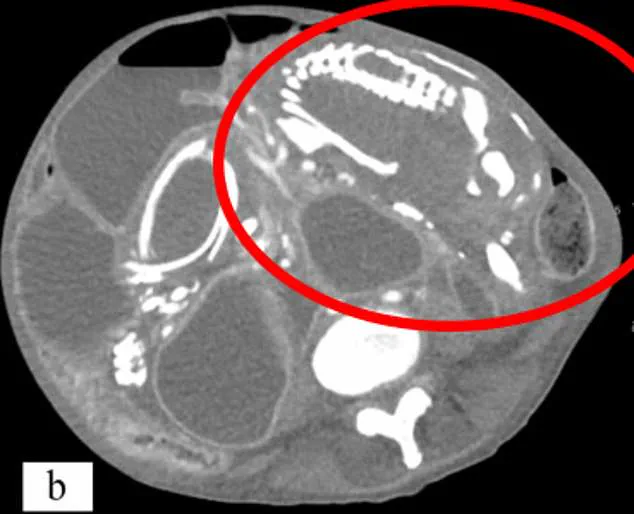

Last week's episode of *Call The Midwife* brought a rare and heartbreaking medical condition into the spotlight, highlighting a phenomenon known as lithopedion, or 'stone baby.' The storyline, set in the 1970s, depicted a woman experiencing unexplained pain and incontinence, only for surgeons to discover a calcified fetus embedded in her abdomen during a procedure. This condition, though fictionalized in the drama, is rooted in real medical history and has been documented in hundreds of cases worldwide.

Lithopedion is a rare complication of ectopic pregnancy, where a fertilized egg implants outside the uterus, typically in the fallopian tubes. When such a pregnancy fails, the body's immune system often reabsorbs the tissue. However, if the fetus survives beyond 12 weeks, its skeletal structure begins to calcify, forming a hard, stone-like mass. This process, a form of mummification, protects the mother from infection while leaving the calcified fetus trapped in the abdominal cavity for years, even decades.

Historical records show the earliest known lithopedion dates back to 1100 BC, uncovered during an archaeological dig in Texas. Modern cases, however, remain rare, with only 330 documented globally. Dr. Lee notes that advances in prenatal care and imaging technology have made lithopedion even rarer today. Early detection through blood tests and ultrasounds allows for timely intervention, preventing the calcification process from occurring.